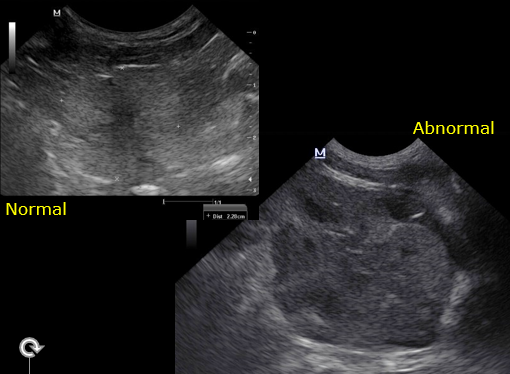

What is the normal appearance of prostate ultrasound?

What is this appearance?

Immature Hypoechoic

Discuss the appearance here

Mature – hard to make out margin

Smooth and rounded

Under 2cm

How does the overall echogenicity compare to the normal prostate?

What is the liekly differential?

Heterogenous

More echogenic

Bigger too

Diagnosis:

BPH

Cant rule out infection = not many cysts